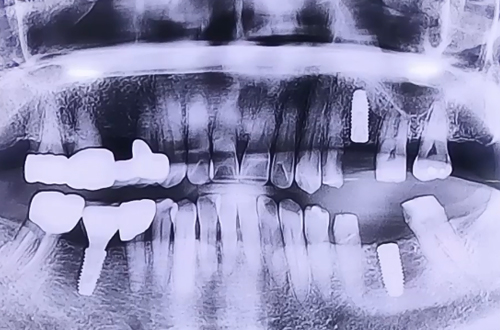

브릿지 재건 후 임플란트

브릿지가 오래되면서 힘을 잃어 오른쪽으로만 식사를 해온 환자분이십니다.

브릿지 제거 후 위아래 남은 양옆의 치아들은 보철로 이를 둘러 씌워주고 임플란트 치료를 마무리해드렸습니다.

추후 이플란트가 주변 뼈들과 단단하게 굳고 나면 임플란트 위쪽으로 어금니를 예쁘게 제작해 드릴 예정입니다.

3개월 후 보철이 완성된 이후 다음 진료일지로 찾아뵙도록 하겠습니다!